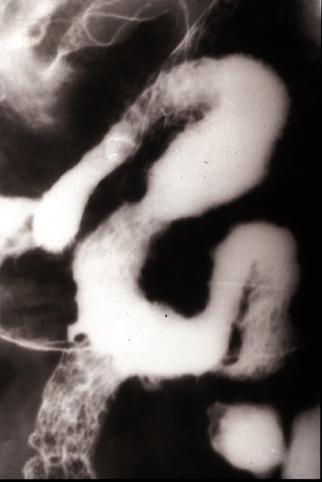

疾病(病理主体)的分类寄生虫疾患/粪便线虫病

部位(按器官分)小肠/2个以上

检查方法X线

肿瘤最大直径40以上